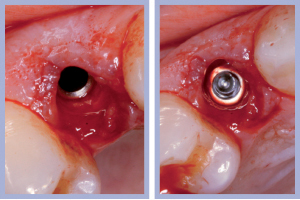

- Figg. 11a, b – Inserimento dell’impianto di destra. Max Stability da 3,75 x 12 mm

- Figg. 12a, b – Impianto di destra inserito

- Figg. 13a, b – Inserimento dell’impianto di sinistra. Max Stability da 3,75 x 12 mm

- Figg. 14a, b – Impianto di sinistra inserito

Il posizionamento di due impianti Max Stability da 3,75 mm di diametro e 12 mm di lunghezza ha consentito l’ottenimento di una elevata stabilità primaria, essenziale per portare a termine il carico immediato programmato. Nel caso dell’impianto Max Stability, la forma tronco-conica è associata alla presenza di spire molto prominenti che garantiscono un’elevata stabilizzazione anche in osso di qualità scadente.